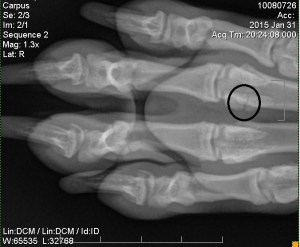

The x-rays revealed a fracture on her right “knuckle” bone. The official diagnosis:

“transverse fracture of axial sesamoid 4th metacarpophalyngeal joint with minimal displacement. The fracture is undisplaced so should heal quickly.”

Whew! that is a mouthful. In short, it is a simple fracture that should heal properly after wearing a splint for 3-4Β weeks.